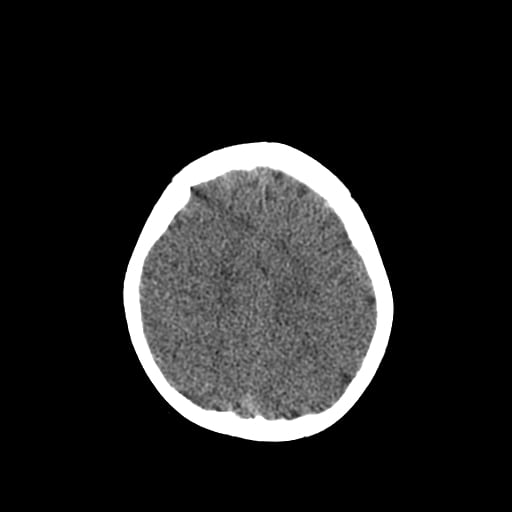

Age: 1

Sex: Male

Indication: Fall